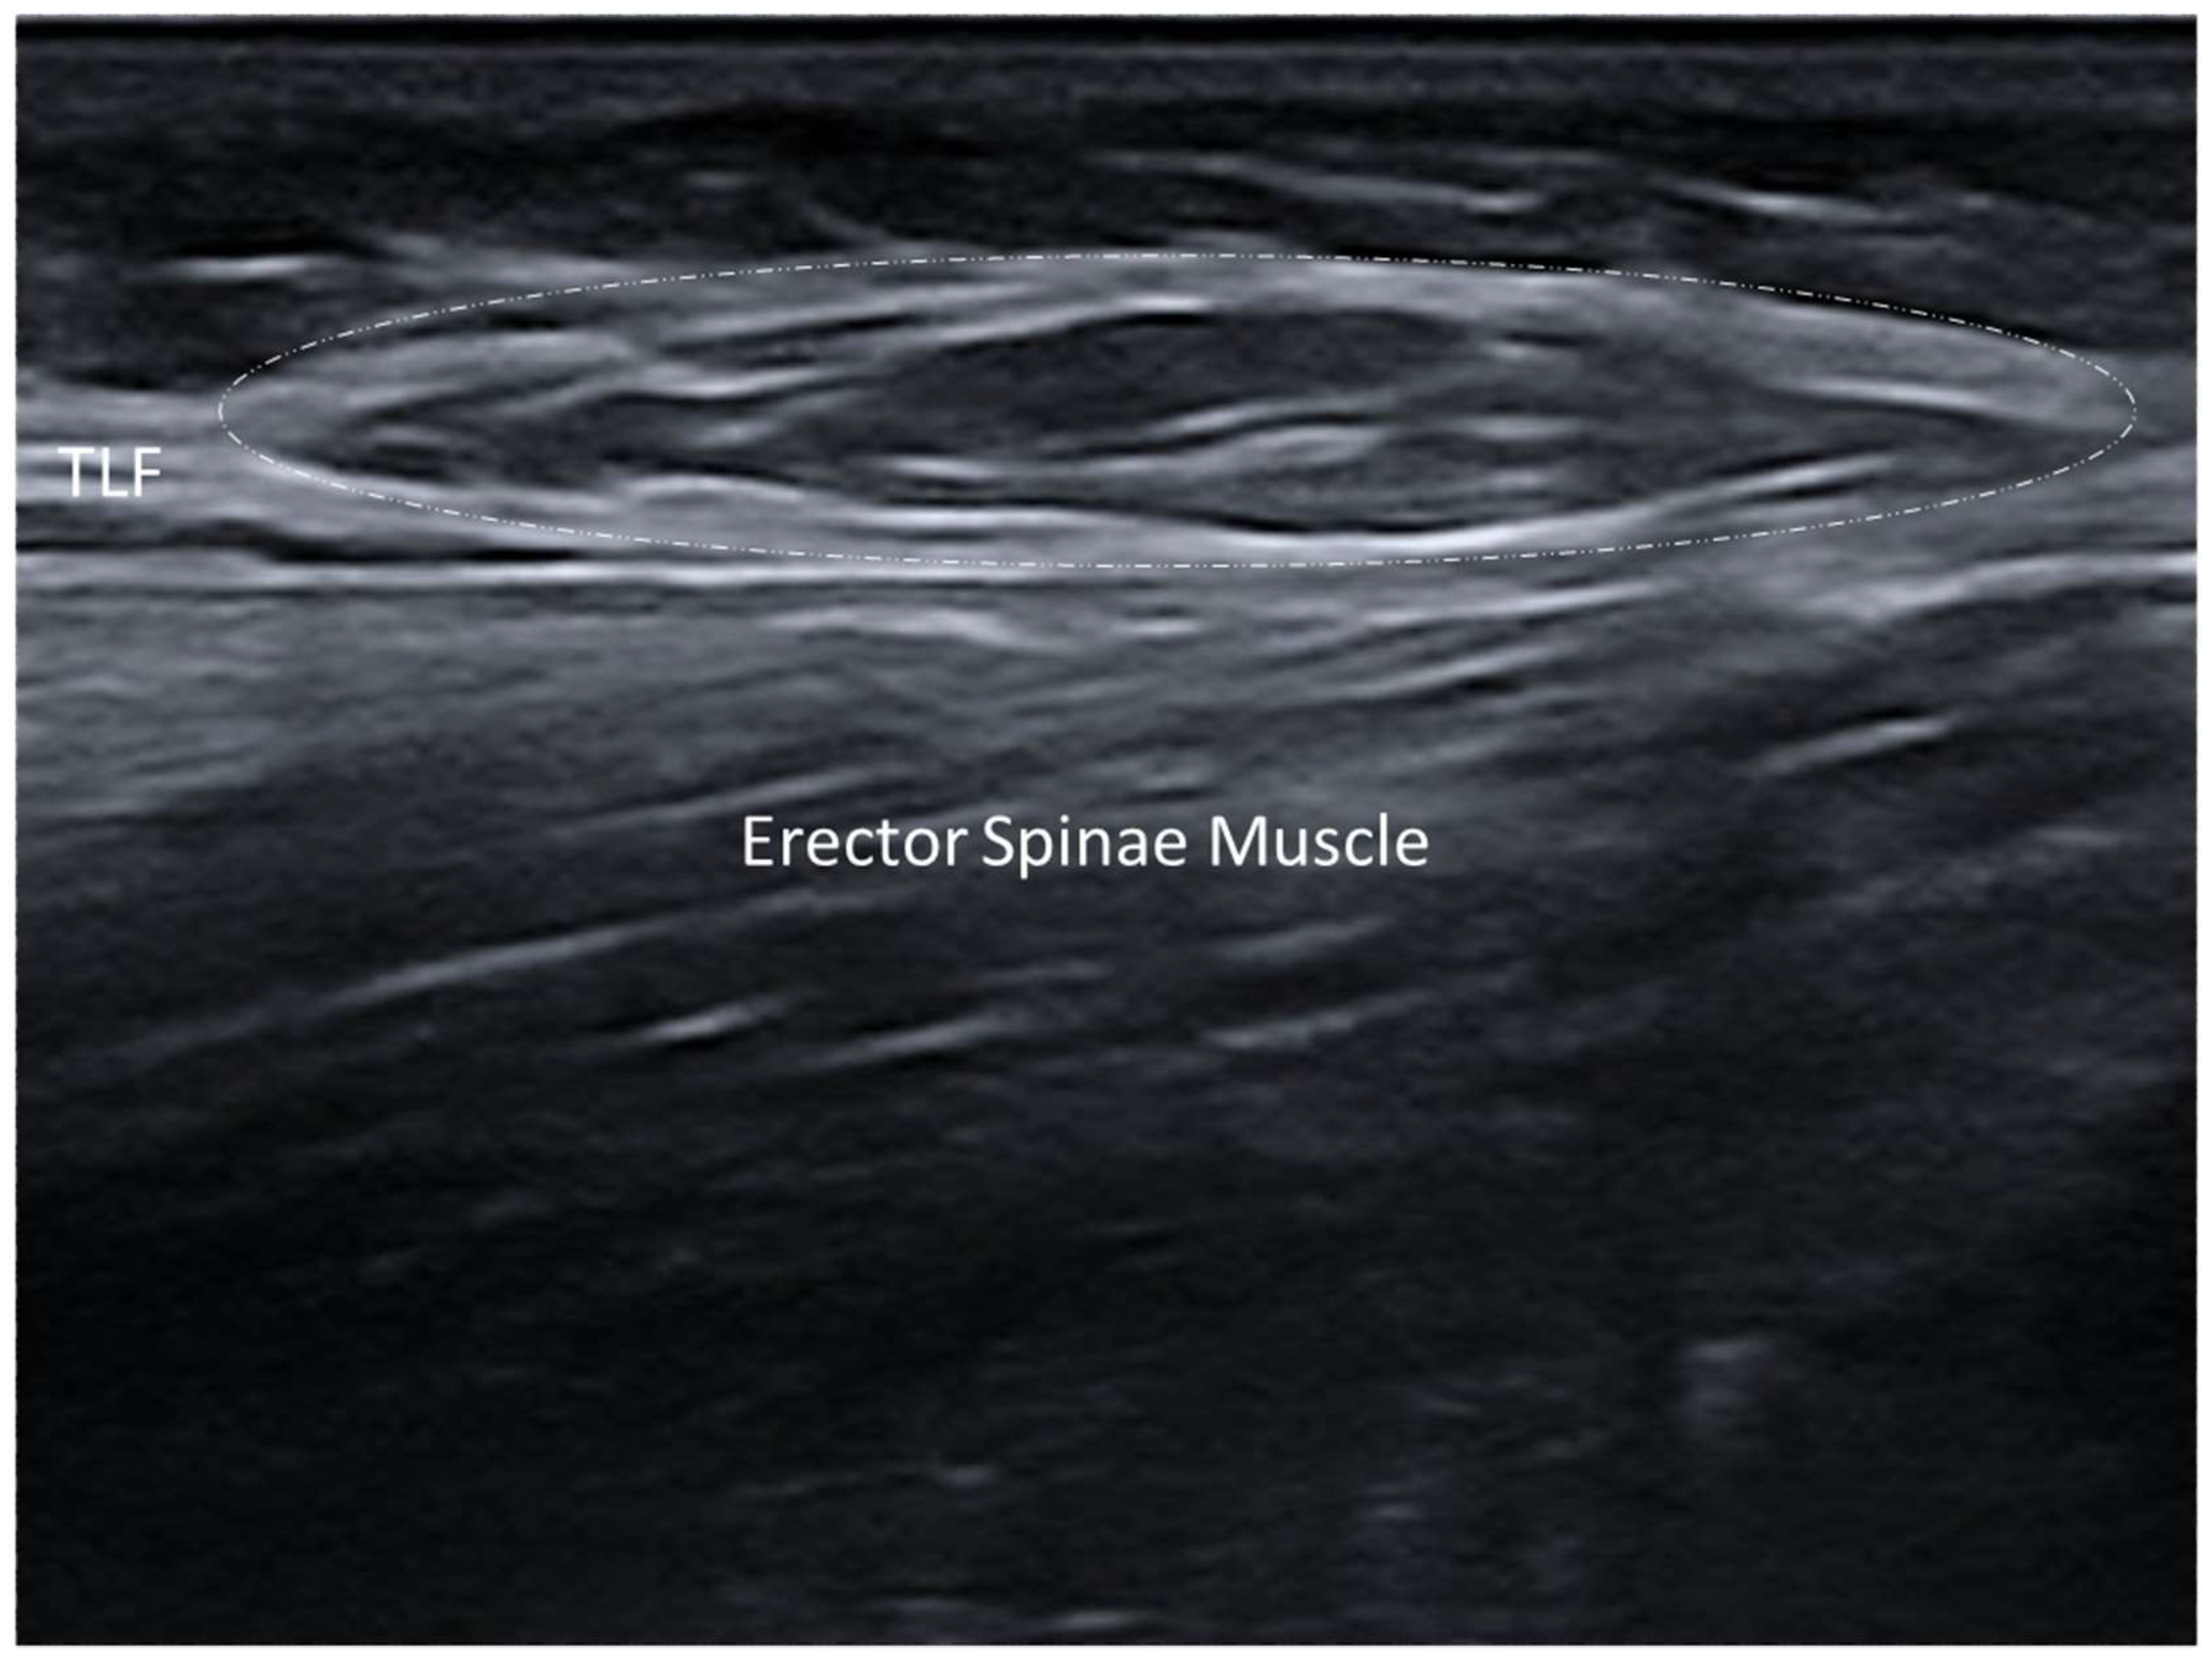

3.1. Normal Ultrasonographic Appearance of Fasciae

- Pirri, C.; Pirri, N.; Guidolin, D.; Macchi, V.; Porzionato, A.; De Caro, R.; Stecco, C. Ultrasound Imaging of Thoracolumbar Fascia Thickness: Chronic Non-Specific Lower Back Pain versus Healthy Subjects; A Sign of a “Frozen Back”? Diagnostics 2023, 13, 1436. [Google Scholar] [CrossRef] [PubMed] [PubMed Central]